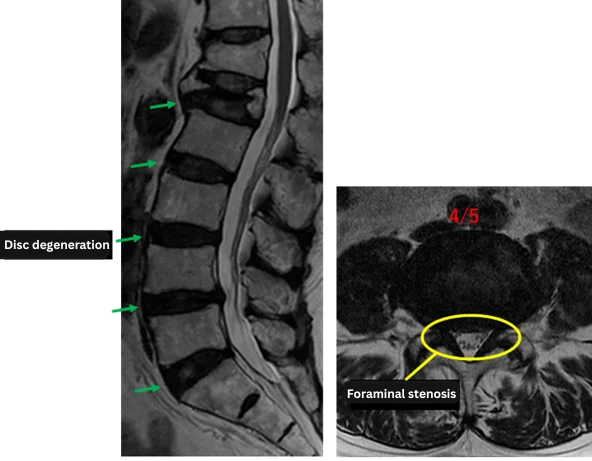

L1/2: Disc degeneration

L2/3: Disc degeneration

L3/4: Disc degeneration, disc bulging

L4/5: Disc degeneration, disc bulging, bilateral foraminal stenosis

L5/S: Disc degeneration, annular tear

The above findings were also observed on the imaging.

These findings indicate that degeneration, disc bulging, and bilateral foraminal stenosis at L3/4, L4/5, and L5/S are highly likely to be the primary cause of symptoms.